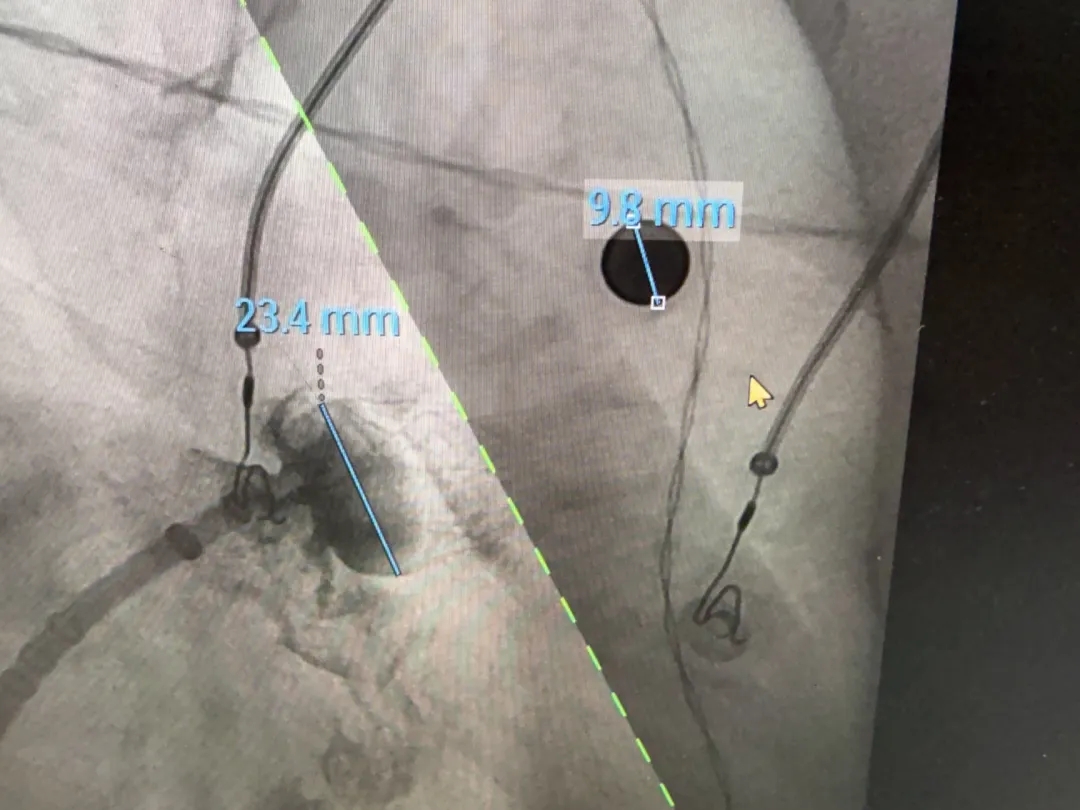

术中DSA肝位造影:双分叶鸡翅型左心耳

肝位造影,心房侧显影,轴向偏前,下缘早分叶

开口23.5mm,深度18.1mm

压缩比测量

压缩比17.3%,在10%-30%之间,符合推荐压缩比